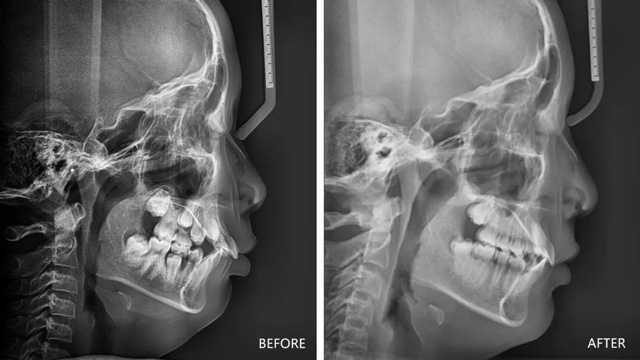

儿童下巴后缩治疗前后

我们通过正畸治疗把下颌导出,恢复到正常的面型比例和上下颌的对应关系,就可以很好地改善以上情况。网友关注的这位女孩的情况是一个II类错颌畸形,同时是高角面型,错颌畸形是一种口腔疾病,确实需要治疗。